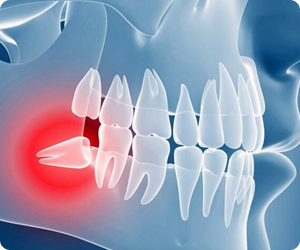

If you do not extract your wisdom teeth and they continue to give you agony, they may become impacted. Your dental health may deteriorate and you may experience excruciating pain from impacted wisdom teeth. The symptoms and indicators are easy to identify: pain, inflammation, and a broad range of diseases.